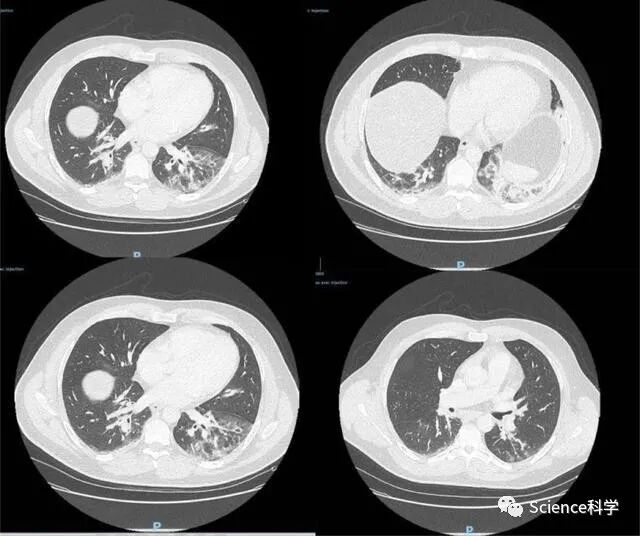

2019年7月,德克里特堡基地被突然关闭。就在基地关闭前一个多月,距离该基地一小时车程的一所养老院爆发了一场神秘的传染病,养老院中的老人均出现与感染新冠肺炎病人相似的症状——肺部CT扫描结果呈“毛玻璃”状,同时伴有肺炎和发烧的症状。这场神秘的传染病,最终导致养老院中的60多名老人身亡。

患者CT

2019年8月,美国疾病与控制中心(CDC)以该基地没有遵守安全守则,强行停止了该基地的所有研究;但是在涉及泄露病毒细节时,CDC以国家安全的名义,对所有细节进行保密。在CDC公布的调查报告中显示,该基地总共有六项违反安全条例的行为,其中包括实验废水净化系统失灵和操作程序不规范的违规行为。